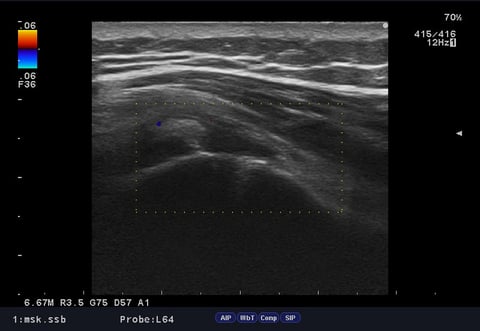

そのため、エコー(超音波)検査を実施したところ、

**腱板部に石灰の沈着(石灰陰影)**が確認され、

👉 石灰沈着性腱板炎と判断しました。